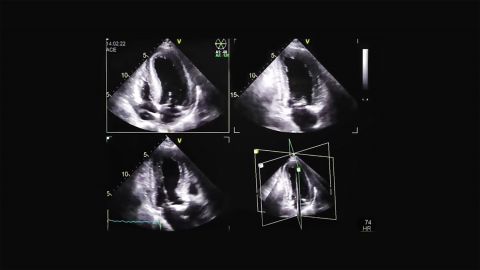

prof. dr hab. n. med. Jarosław KasprzakDane kliniczne:Pacjent z niewydolnością serca i przewlekłym zespołem wieńcowymRozpoznanie główne:Amyloidoza transtyretynowaNiewydolność serca z zachow...